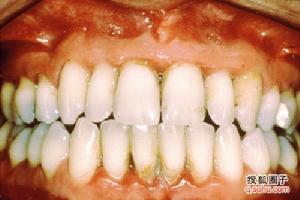

牙周萎縮是指全口牙廣泛的齦緣與牙槽骨同時退縮,牙根暴露,但無明顯炎症和創傷。過去認為這是生理性的增齡變化,稱為老年性牙周萎縮。症狀體徵

牙周萎縮的程度因人而異,幾乎所有的老年人全口牙周組織都有均勻性退縮。臨床表現為牙槽骨高度降低,牙齦退縮,但無明顯炎症。由於牙根暴露,常可發生牙本質敏感症、牙頸部齲和根面齲。齲楔狀間隙增大,易發生水平型食物嵌塞,從而易產生炎症,加重牙齦退縮。疾病病因